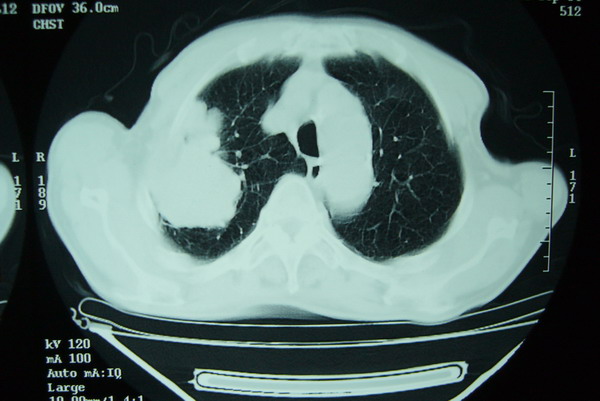

标题: CT15579:男 86岁 咳嗽 咳少量白痰 发热2天 吸烟史60年 [打印本页]

标题: CT15579:男 86岁 咳嗽 咳少量白痰 发热2天 吸烟史60年

右上周围型肺癌,慢支,肺气肿。

分叶及少量边缘性钙化,老年人,周围性肺癌首先考虑。

右肺上叶巨大软组织肿块,轮廓不规则,纵隔内有肿大淋巴结,首先考虑肺癌。

右上肺一不规则团块,边缘有分叶和毛刺,纵隔有淋巴结肿大。右肺周围性肺癌首先考虑。